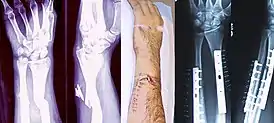

Рентгеновское исследование позволяет более точно установить вид перелома и положение отломков. Рентгенография — стандартный метод диагностики при подтверждении перелома. Именно наличие рентгеновского снимка повреждённого участка служит объективным подтверждением факта перелома. На снимке должны быть изображены два сустава, расположенные дистальней и проксимальней места поражения, кость должна быть изображена в двух проекциях, прямой и боковой. При соблюдении этих условий рентгеновское исследование будет адекватным и полноценным, а возможность ошибочной диагностики минимальна.[L 8]

|

На рентгенограмме изображён перелом большеберцовой кости, подвергшийся хирургическому лечению. 4 снимка в 2 проекциях. На первой паре снимков — верхняя треть голени и коленный сустав (сустав, расположенный проксимальней места перелома), на второй паре снимков — голеностопный сустав (сустав, расположенный дистальней места перелома). Большеберцовая кость фиксирована антероградно введённым в костно-мозговой канал гвоздём (UTN — unreamed tibial nail), блокированным 5 винтами. Такая конструкция позволяет фиксировать отломки и обеспечивает адекватную регенерацию. После формирования костной мозоли металлофиксатор удаляется.